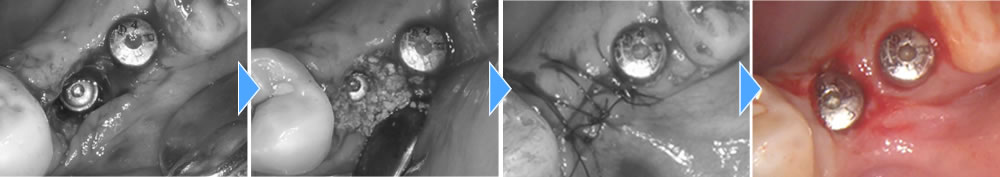

インプラント手術の実施

レントゲンでの検査の結果、抜歯後の予後が悪かったため、インプラントの持ちを良くするために骨造成を同時に行っています。